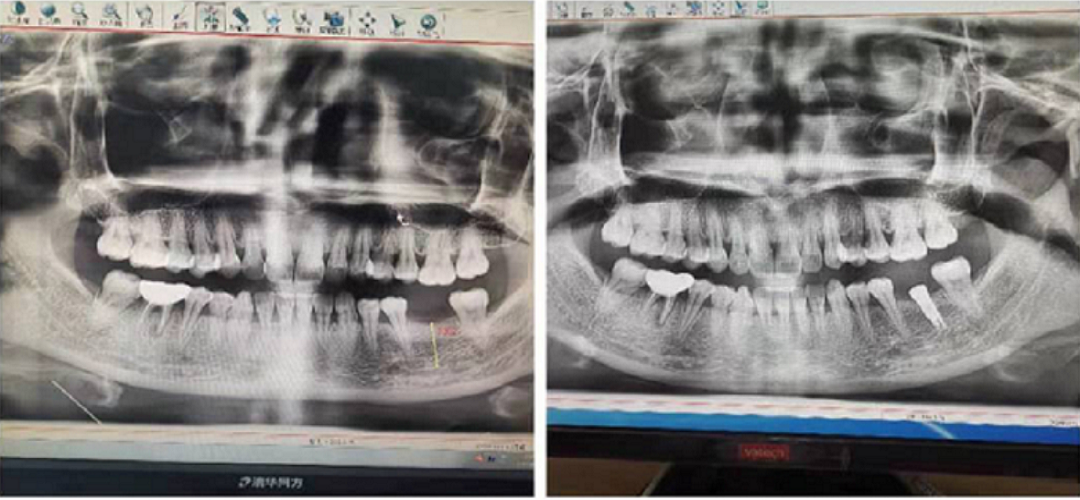

實操體驗結束后,張杰博士對一位左下缺失兩年6牙位的美女,種了一顆金泰克的直徑4mm長度10mm 的微創(chuàng)植體。手術過程體中詳細給學員介紹了操作方法,患者整個過程中體驗了無翻瓣的流血的創(chuàng)傷和術后疼痛少,可以正常進食。